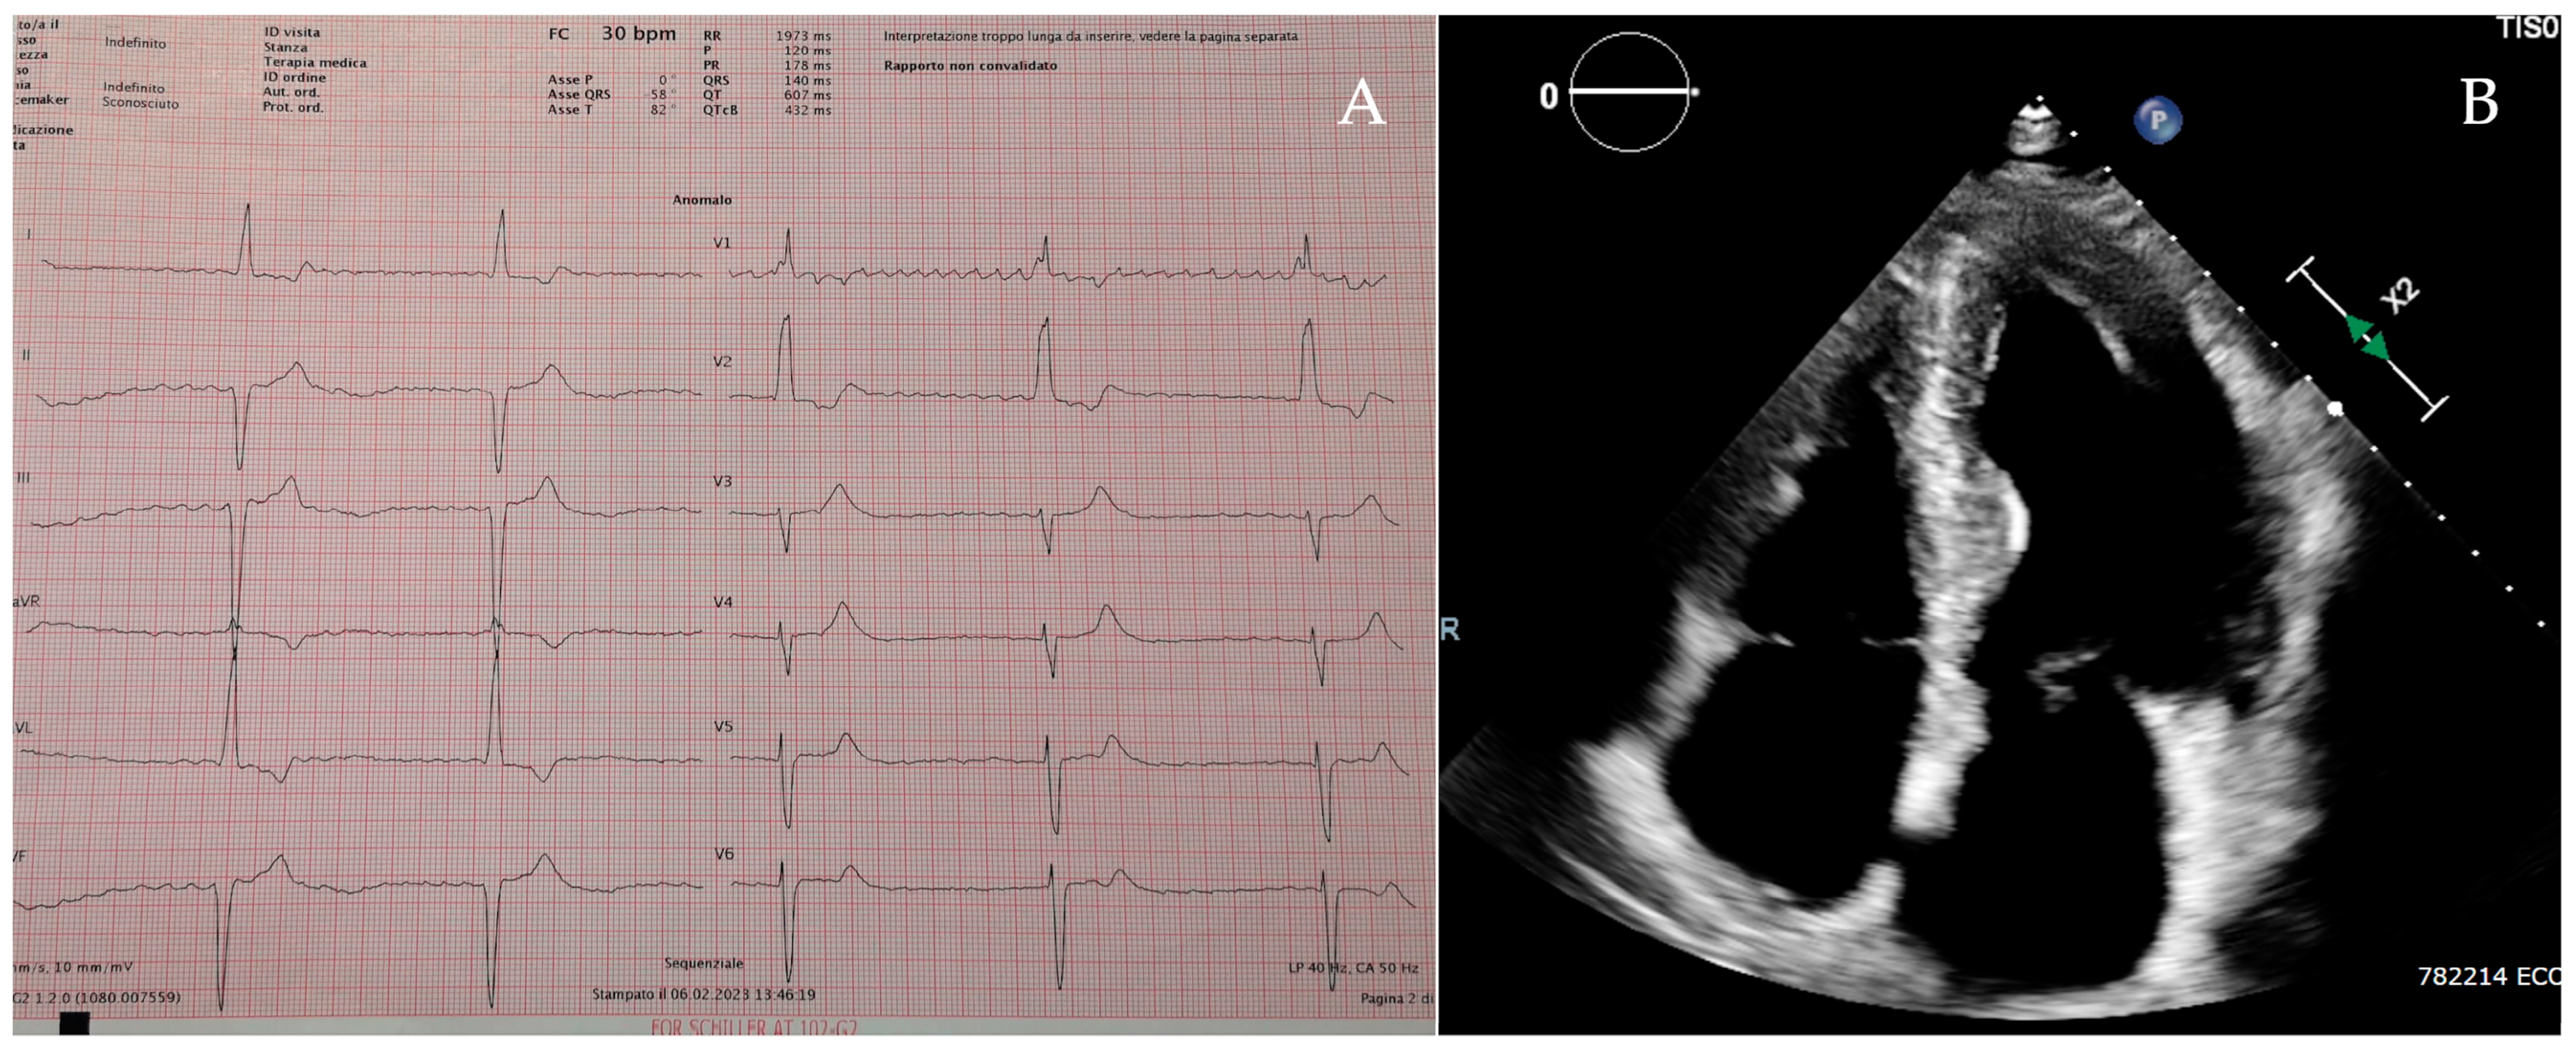

Patient 1 was a 70-year-old man admitted to the hospital with fatigue and shortness of breath. The 12-lead electrocardiogram showed a rhythm of atrial fibrillation complicated with a third-degree atrioventricular block and a ventricular rate of 30 beats per minute (Figure 2A), which required an urgent dual-chamber pacemaker implantation. The echocardiographic assessment revealed a severe LVH with a concentric pattern and an LVMWT of 20 mm at the level of the interventricular septum (Figure 2B), preserved left ventricular ejection fraction, severe left atrial enlargement, right ventricular hypertrophy and mildly reduced right ventricular function. The DBS showed a severe reduction in α-galactosidase A activity, and the gene sequencing identified a hemizygous pathogenic variant in the GLA gene: c.644A>G (p. Asn215Ser). CMR (performed with a 6 -week delay after pacemaker implantation) revealed decreased myocardial native T1 values and the presence of LGE in the infero-lateral wall with a subepicardial pattern. After the exclusion of extensive myocardial fibrosis [14], he started enzymatic replacement therapy (ERT).

Figure 2. Patient 1’s electrocardiogram (A) and apical 4-chamber view on the echocardiogram (B).